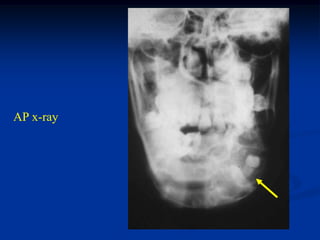

Case #1098

16 year male with

adamantinoma mandible

AP x-ray

Oblique view